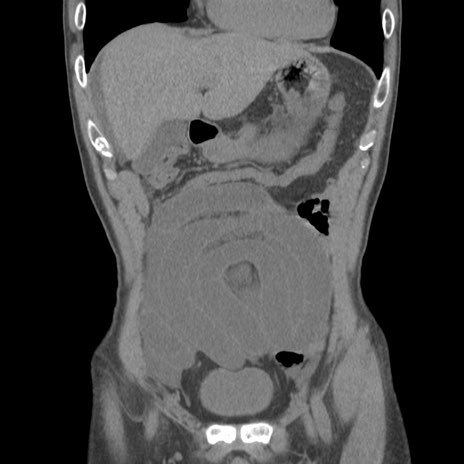

症例56 CT(冠状断像)

脂肪ウインドウ